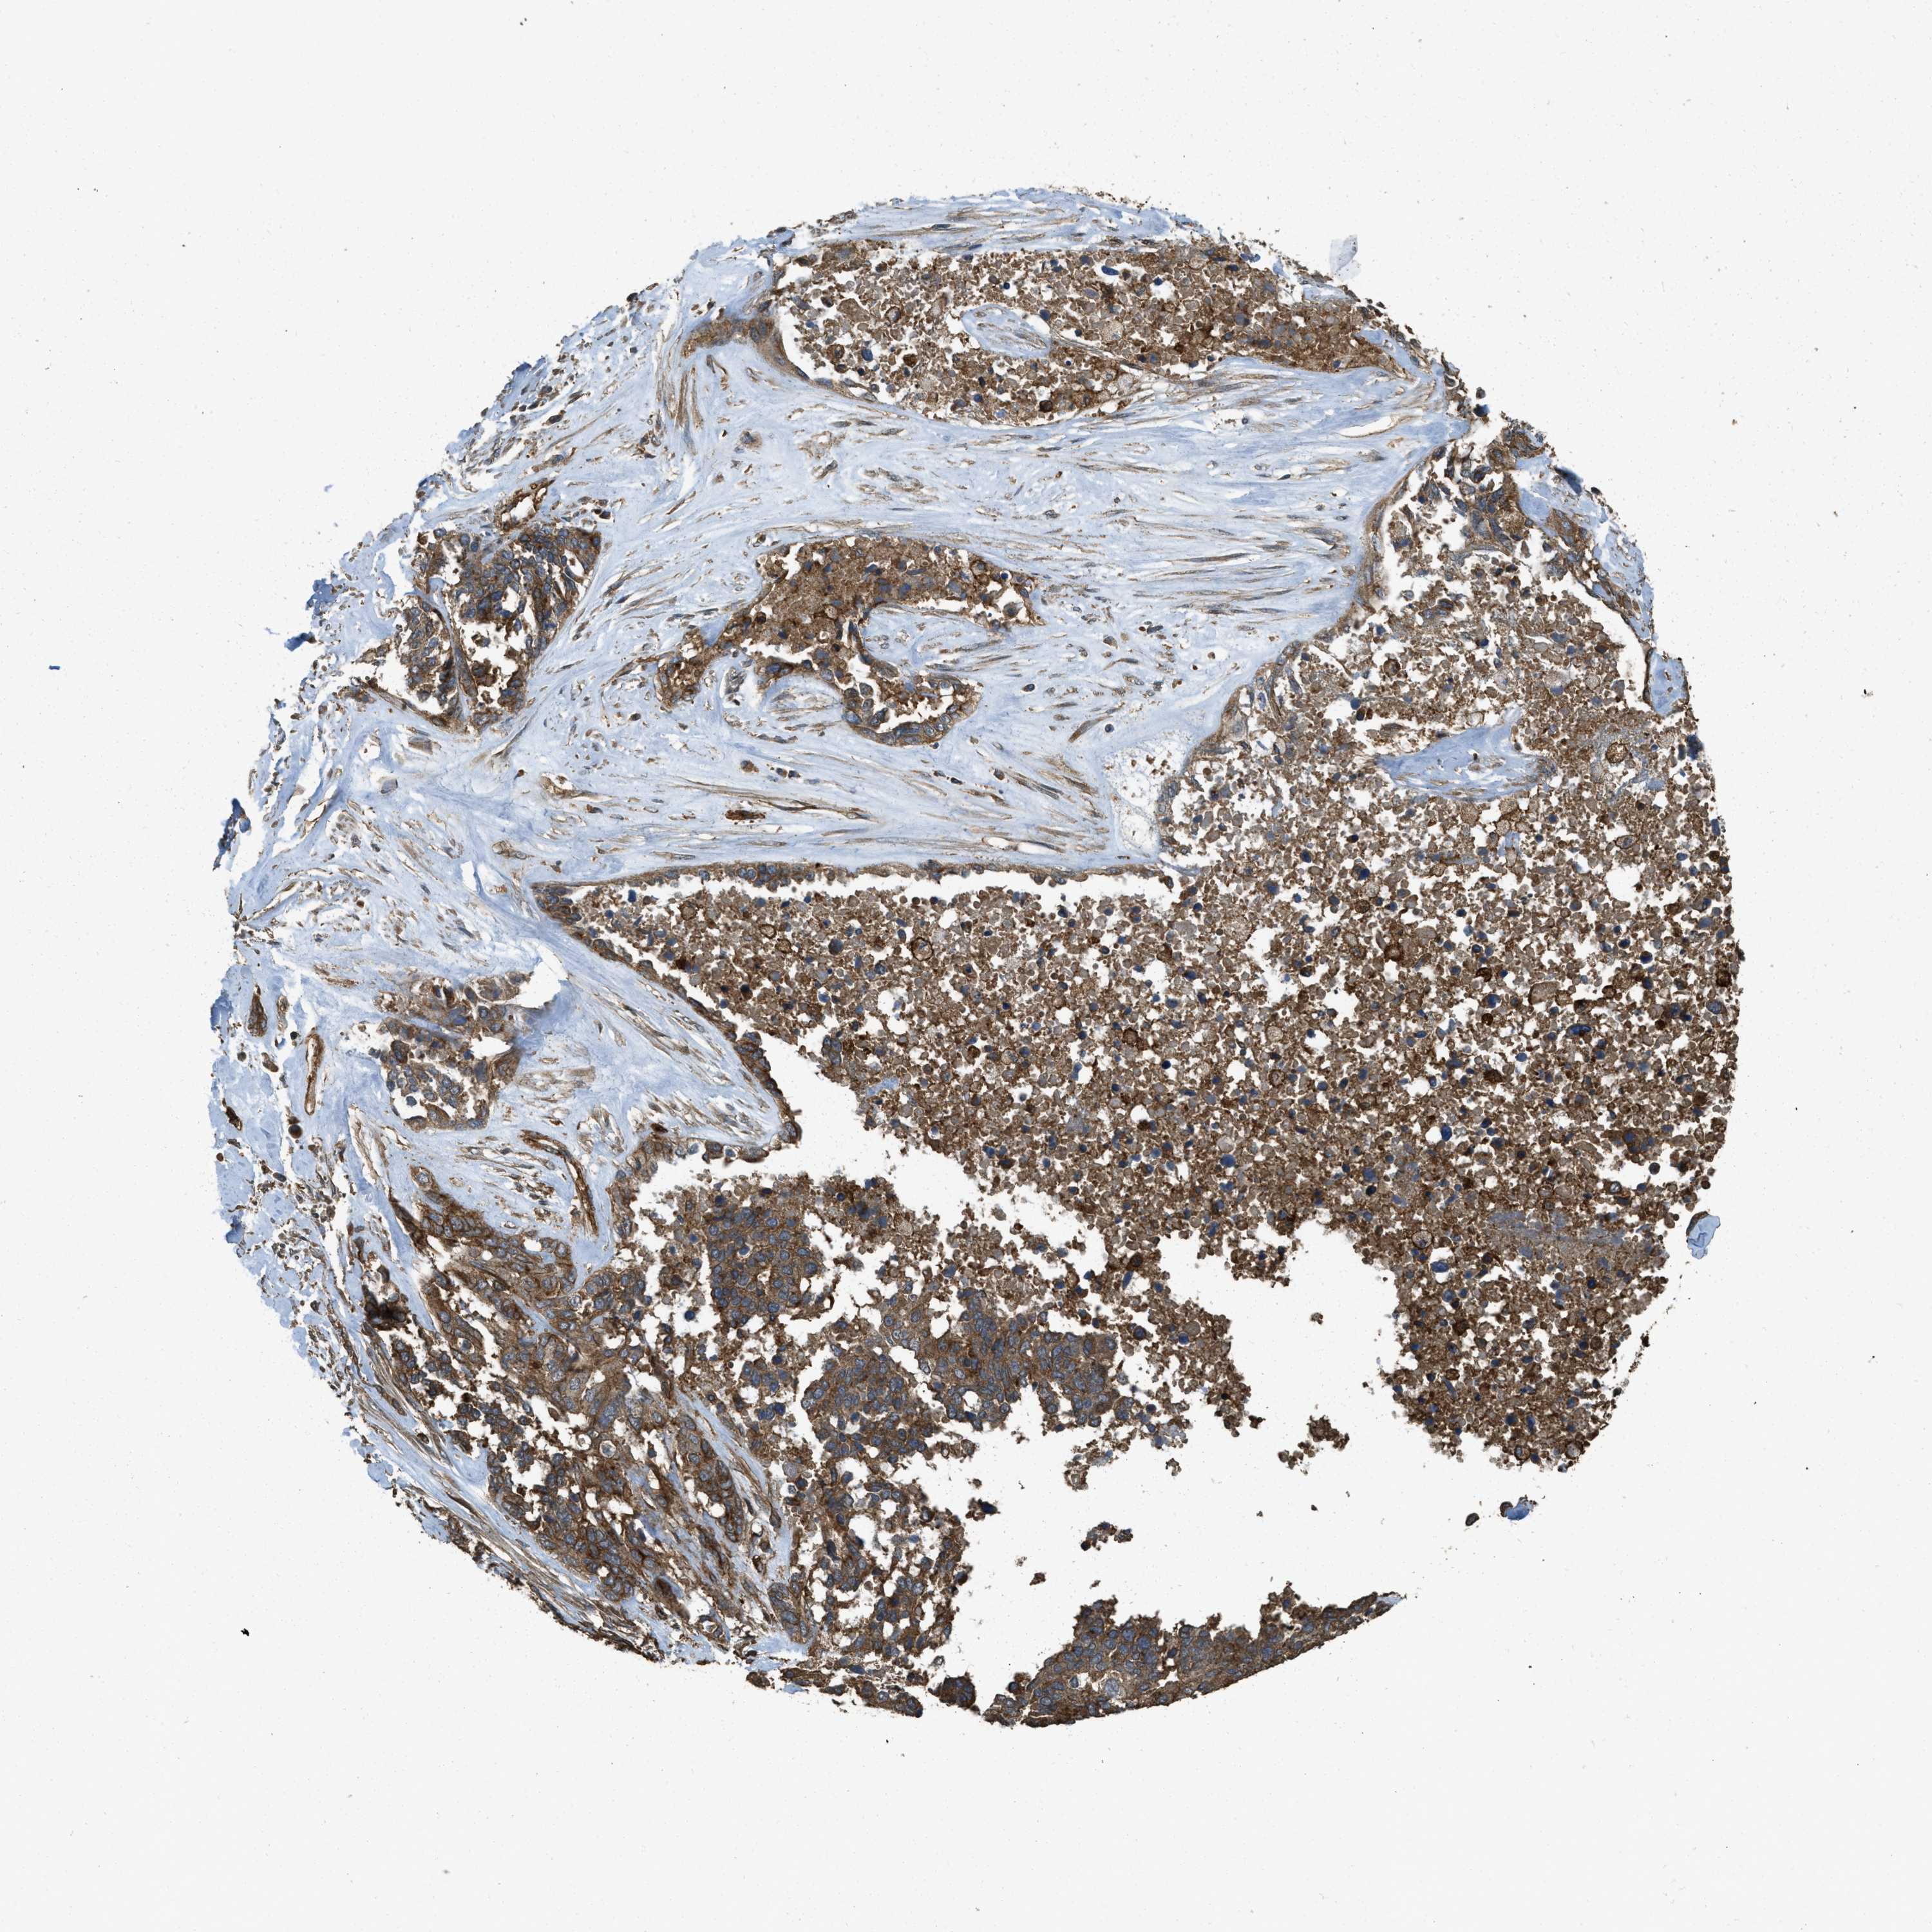

OVARIAN CANCER - Protein expressioni

A mouse-over function shows sample information and annotation data. Click on an image to view it in a full screen mode. Samples can be filtered based on level of antibody staining by selecting one or several of the following categories: high, medium, low and not detected. The assay and annotation is described here.

Note that samples used for immunohistochemistry by the Human Protein Atlas do not correspond to samples in the TCGA dataset.

Antibody stainingi

Antibody staining in the annotated cell types in the current human tissue is reported as not detected, low, medium, or high, based on conventional immunohistochemistry profiling in selected tissues. This score is based on the combination of the staining intensity and fraction of stained cells.

Each image is clickable and will lead to virtual microscopy that enables deeper exploration of all samples and also displays staining intensity scores, fraction scores and subcellular localization as well as patient and tissue information for each sample.

Antibody HPA009285

Antibody HPA017139

Antibody CAB017826

Cystadenocarcinoma, serous, NOS

Carcinoma, endometroid

Cystadenocarcinoma, mucinous, NOS

Carcinoma, NOS